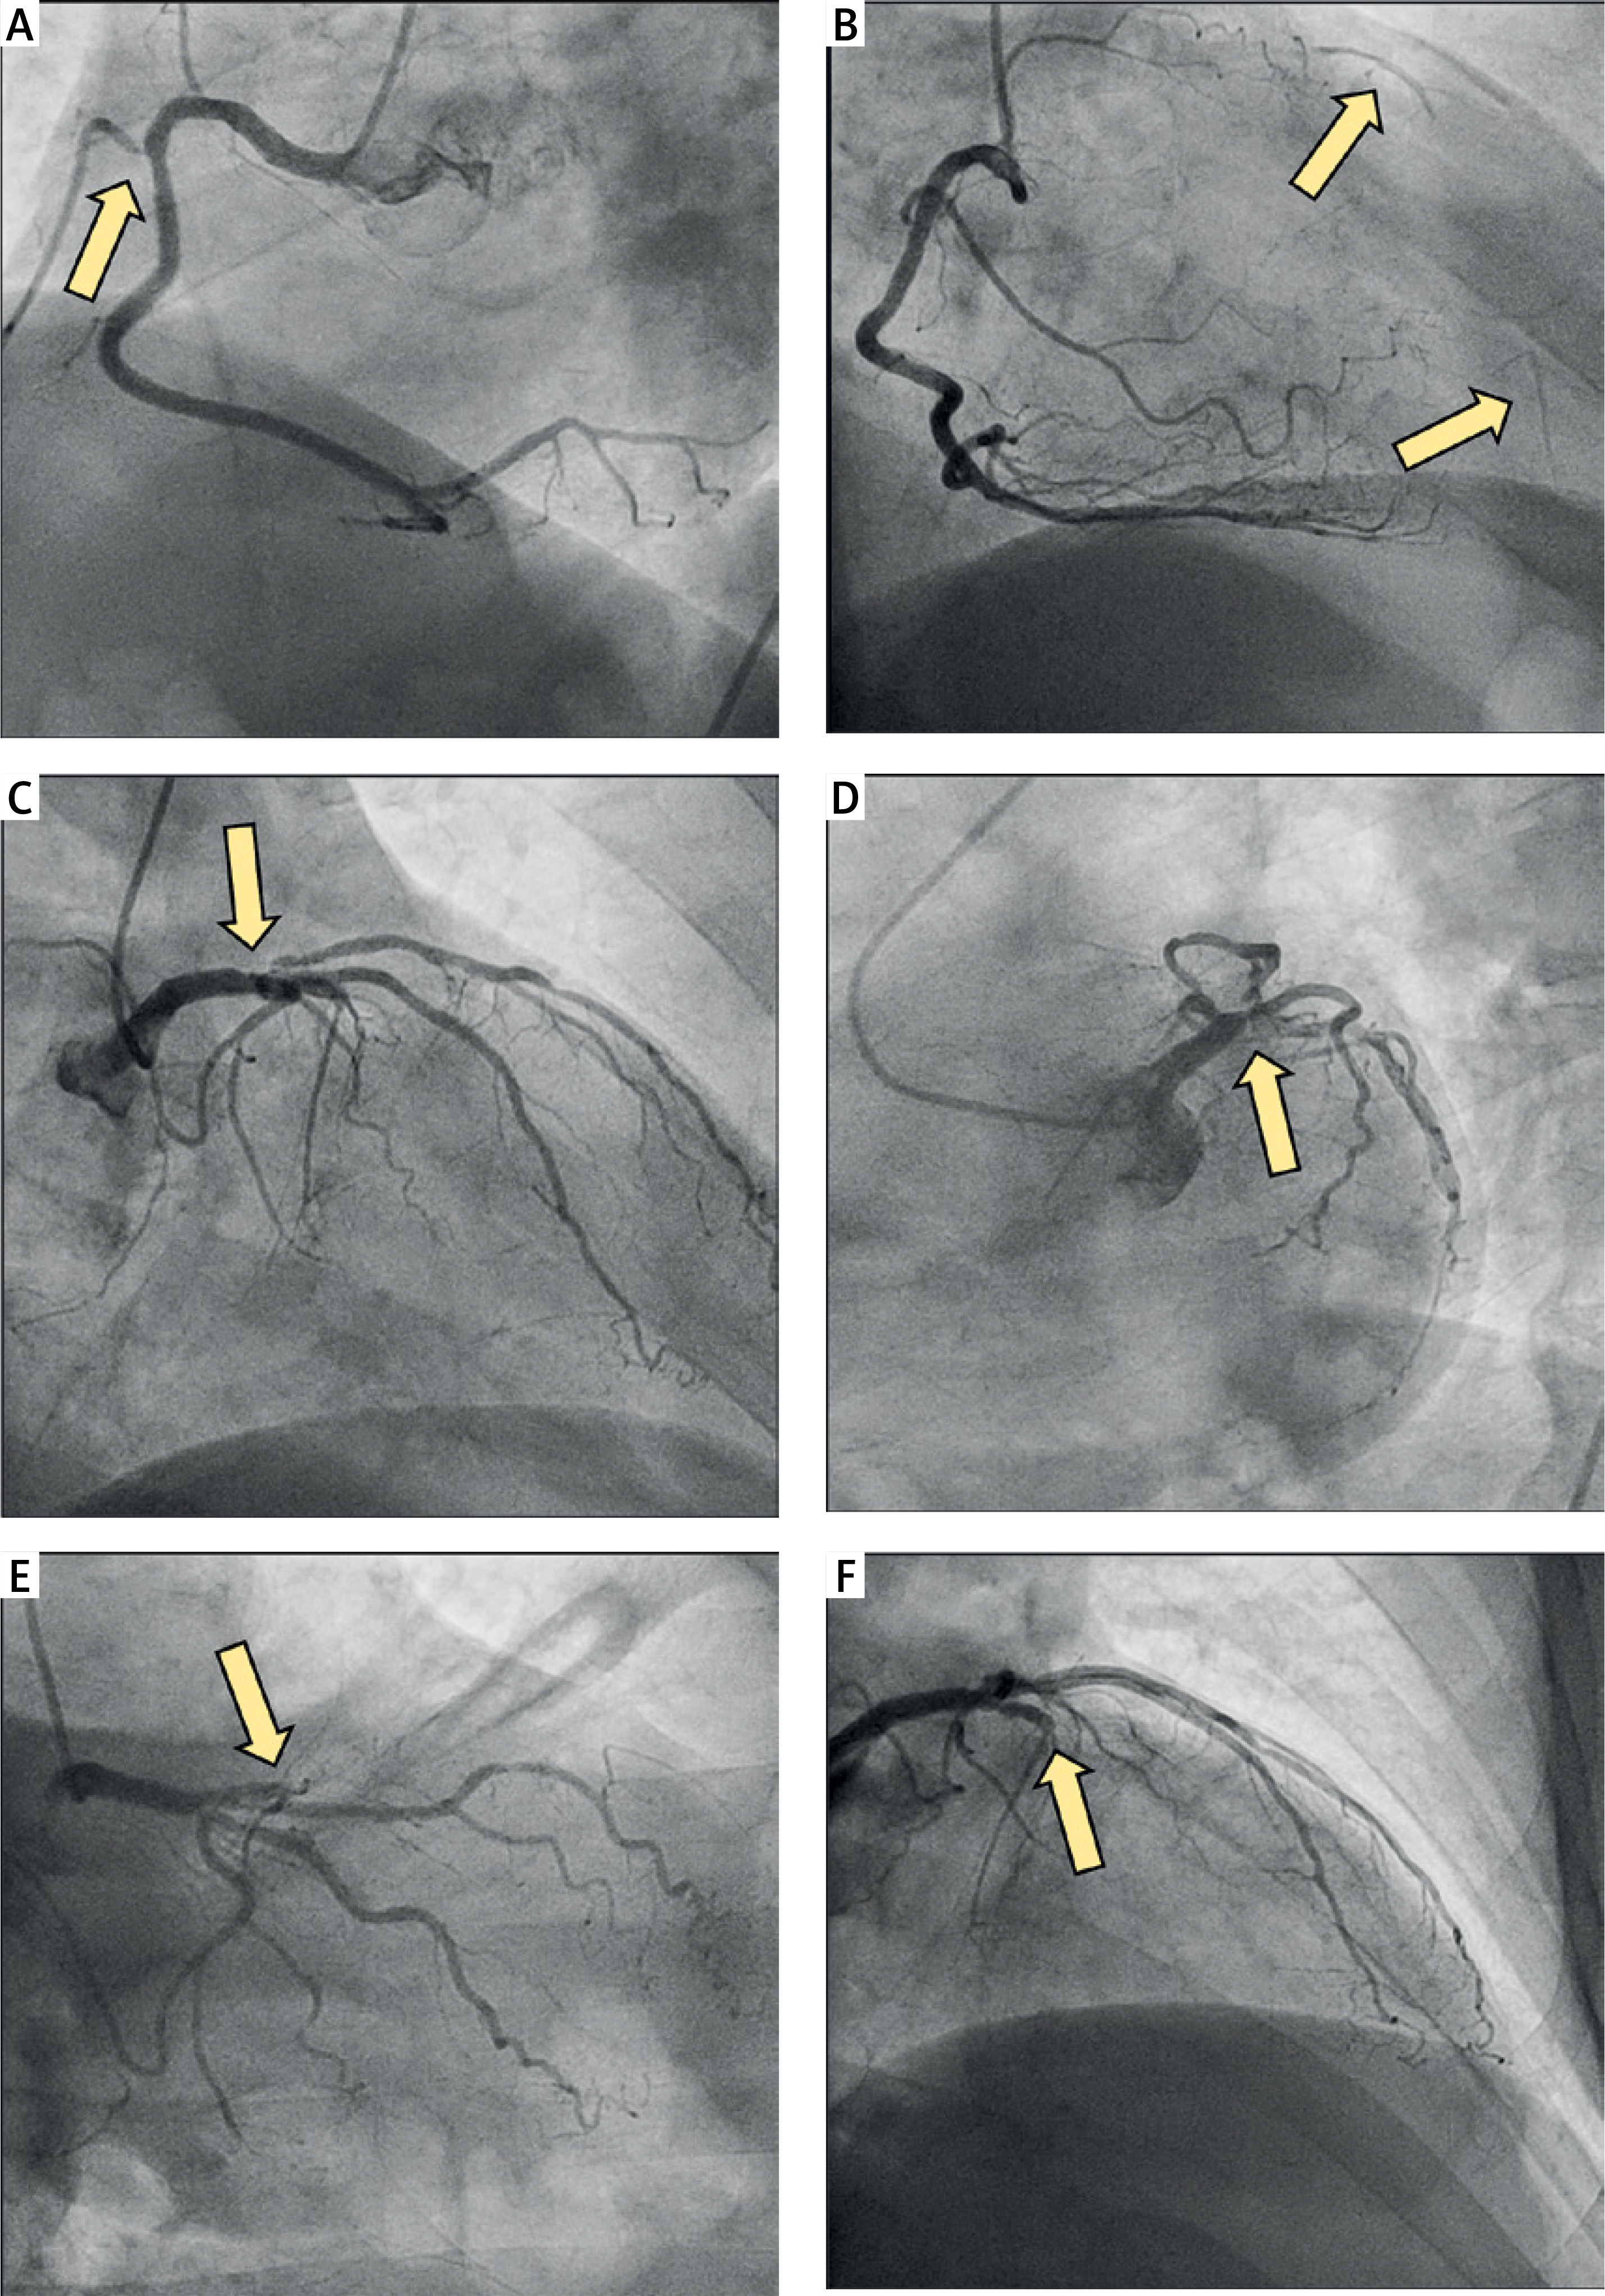

Figure 4

Intraoperative images illustrating the steps of complex left ventricular reconstruction surgery. A – Incision of the anterior left ventricle at the site of the aneurysm. B – Excision of the adherent thrombus from the aneurysmatic region of the left ventricle. C – The resected thrombus removed in its entirety. D – Identification of the margins of the ventricular aneurysm and transition to normal myocardium. E – Suturing of the pericardial patch to reconstruct the left ventricle, reinforcing the transitional zone between scarred and viable myocardium. F – Final placement of the pericardial patch between the aneurysmatic sac and the left ventricular cavity, ensuring optimal ventricular geometry and reducing wall tension. Teflon strips are used to reinforce the closure and prevent further ventricular dilation